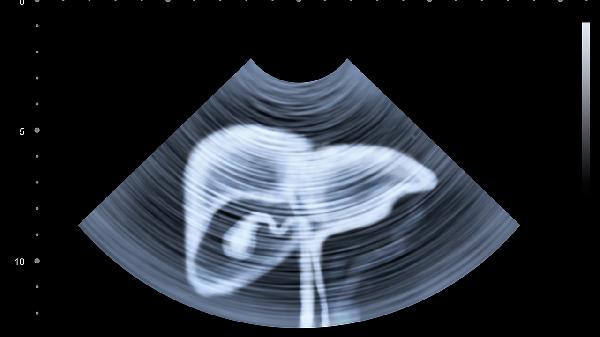

孕20-24周是胎儿器官发育相对成熟的阶段,此时羊水量适中,胎儿活动空间充足,超声影像清晰度高,能够全面观察胎儿颅脑、心脏、脊柱、四肢等结构。23周处于该时间窗内,多数医疗机构会安排此阶段完成检查。检查内容包括测量胎儿双顶径、头围、腹围、股骨长度等生长参数,评估胎盘位置及羊水量,重点排查无脑儿、严重脊柱裂、先天性心脏病等重大畸形。孕妇需提前预约,检查前无须空腹但建议排空膀胱,过程约需30分钟,若胎儿体位不佳可能需短暂活动后重复扫描。